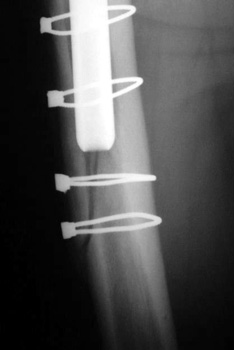

Femoral shaft fracture fixed with cerclage cables.